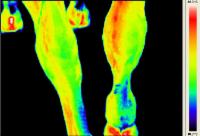

Rasmus - Pferd mit Arthrose - Horse with Osteoarthritis